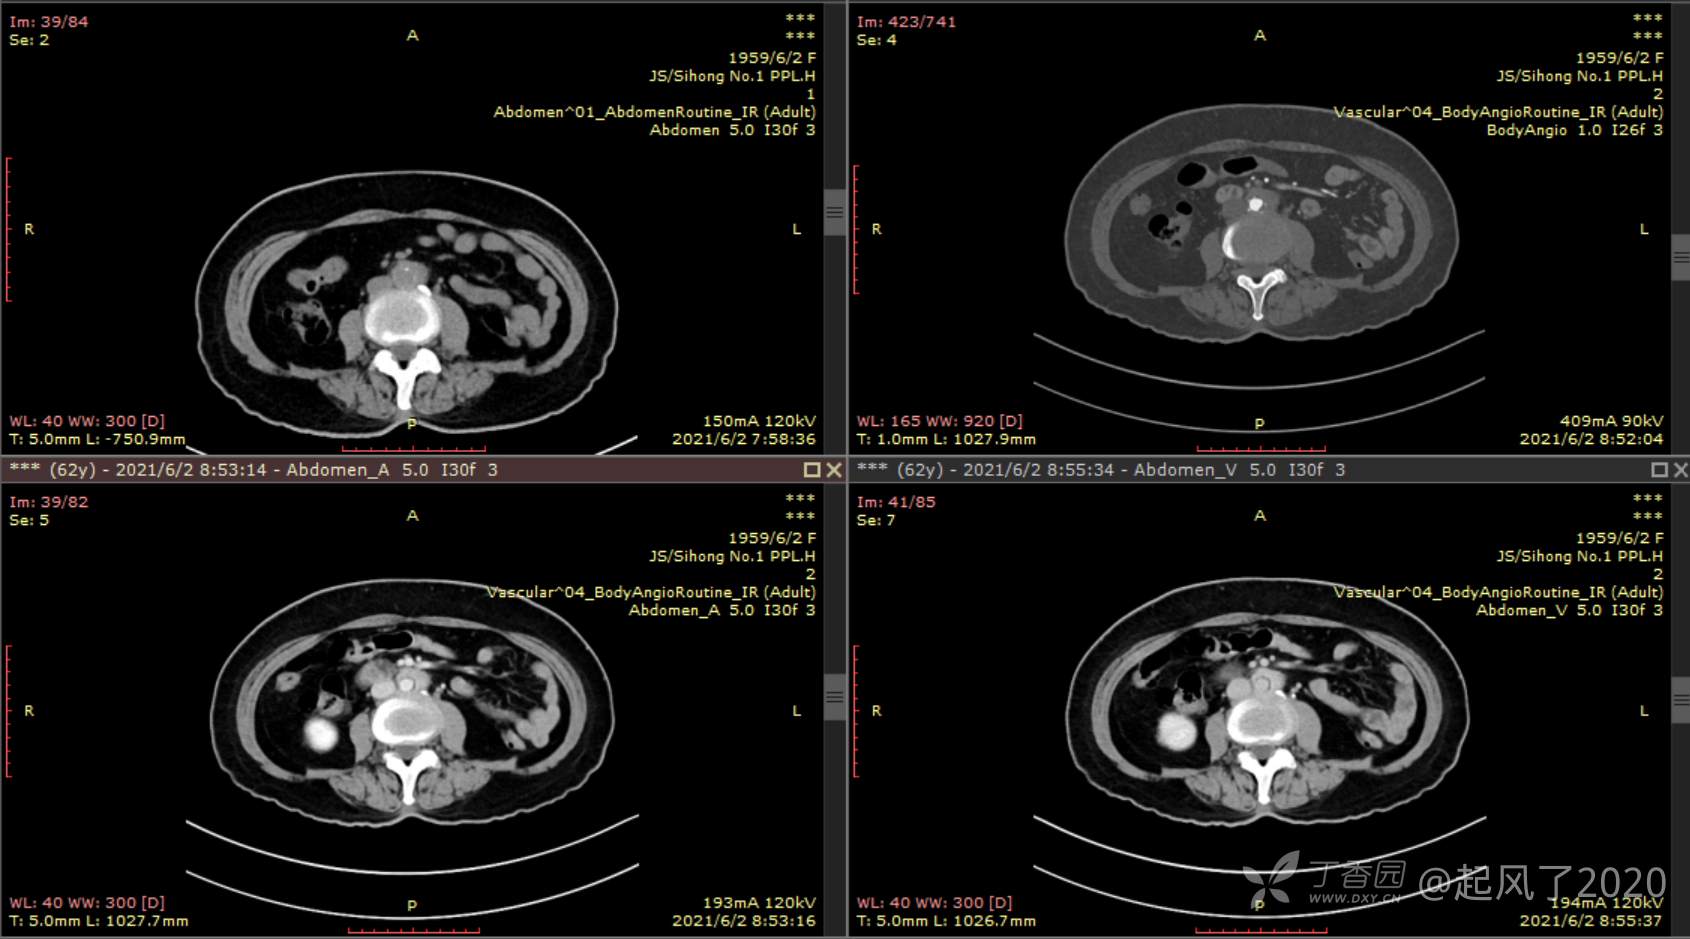

求助 | 女,61岁,下腹部、腰及双髋关节隐痛1月余

II型糖尿病10年余,既往饮食控制血糖在7~8左右,今年1月份开始服用二甲双胍;2009年4月因“子宫肌瘤、双侧输卵管慢性炎症”行子宫及附件切除术;2021年1月体检发现双侧甲状腺多发结节,较大者12*7mm;高血脂10余年,近1月开始规律服药,控制不理想;无高血压